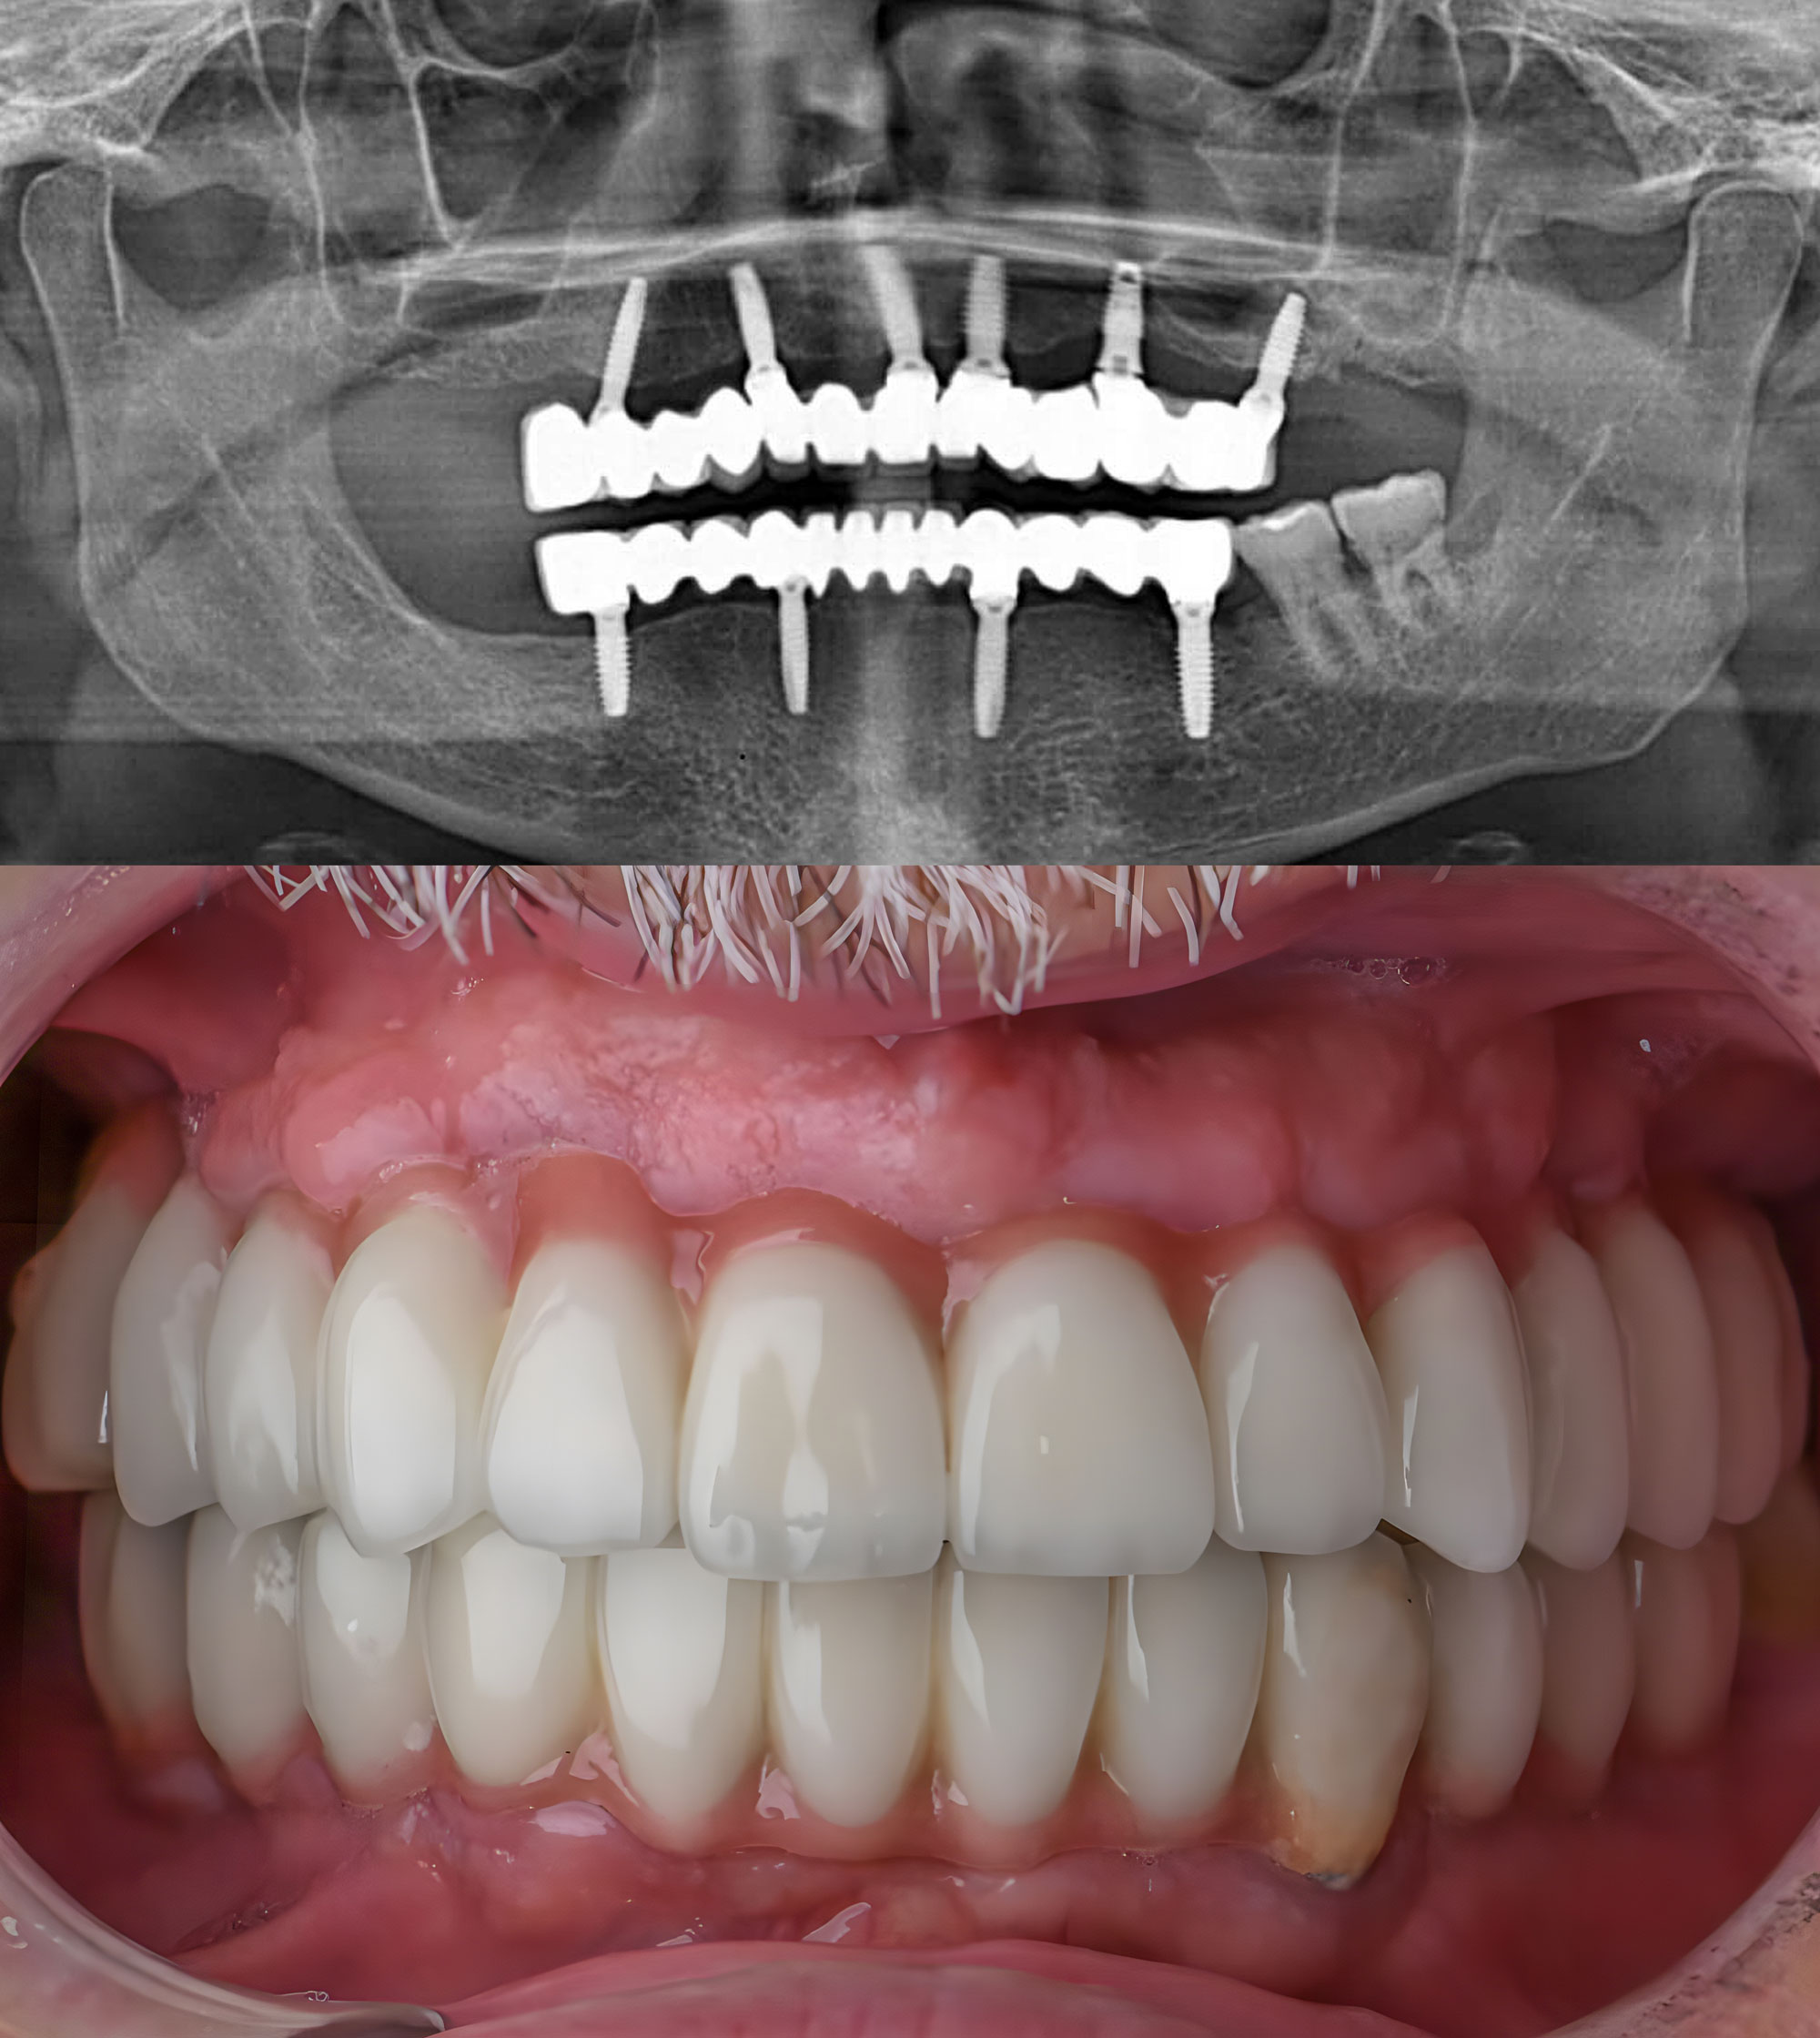

Implant-Supported Restorations Look, Feel, and Function Like Natural Teeth

Incredibly Lifelike Results

The team at our Vancouver, BC, dental practice can craft beautiful, natural-looking restorations. The results will blend seamlessly into your smile and function just like natural teeth.

Strength and Stability

With dental implants, you can feel confident your restoration will stay in place and provide you with the stability and durability you need to enjoy life to the fullest.